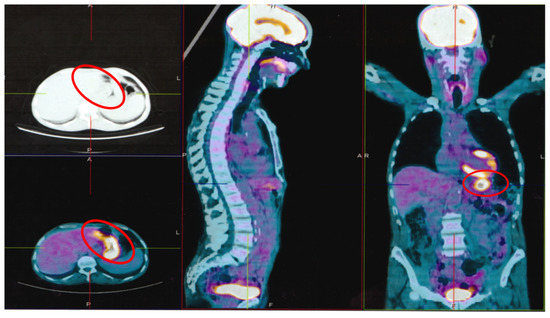

2. Case Report